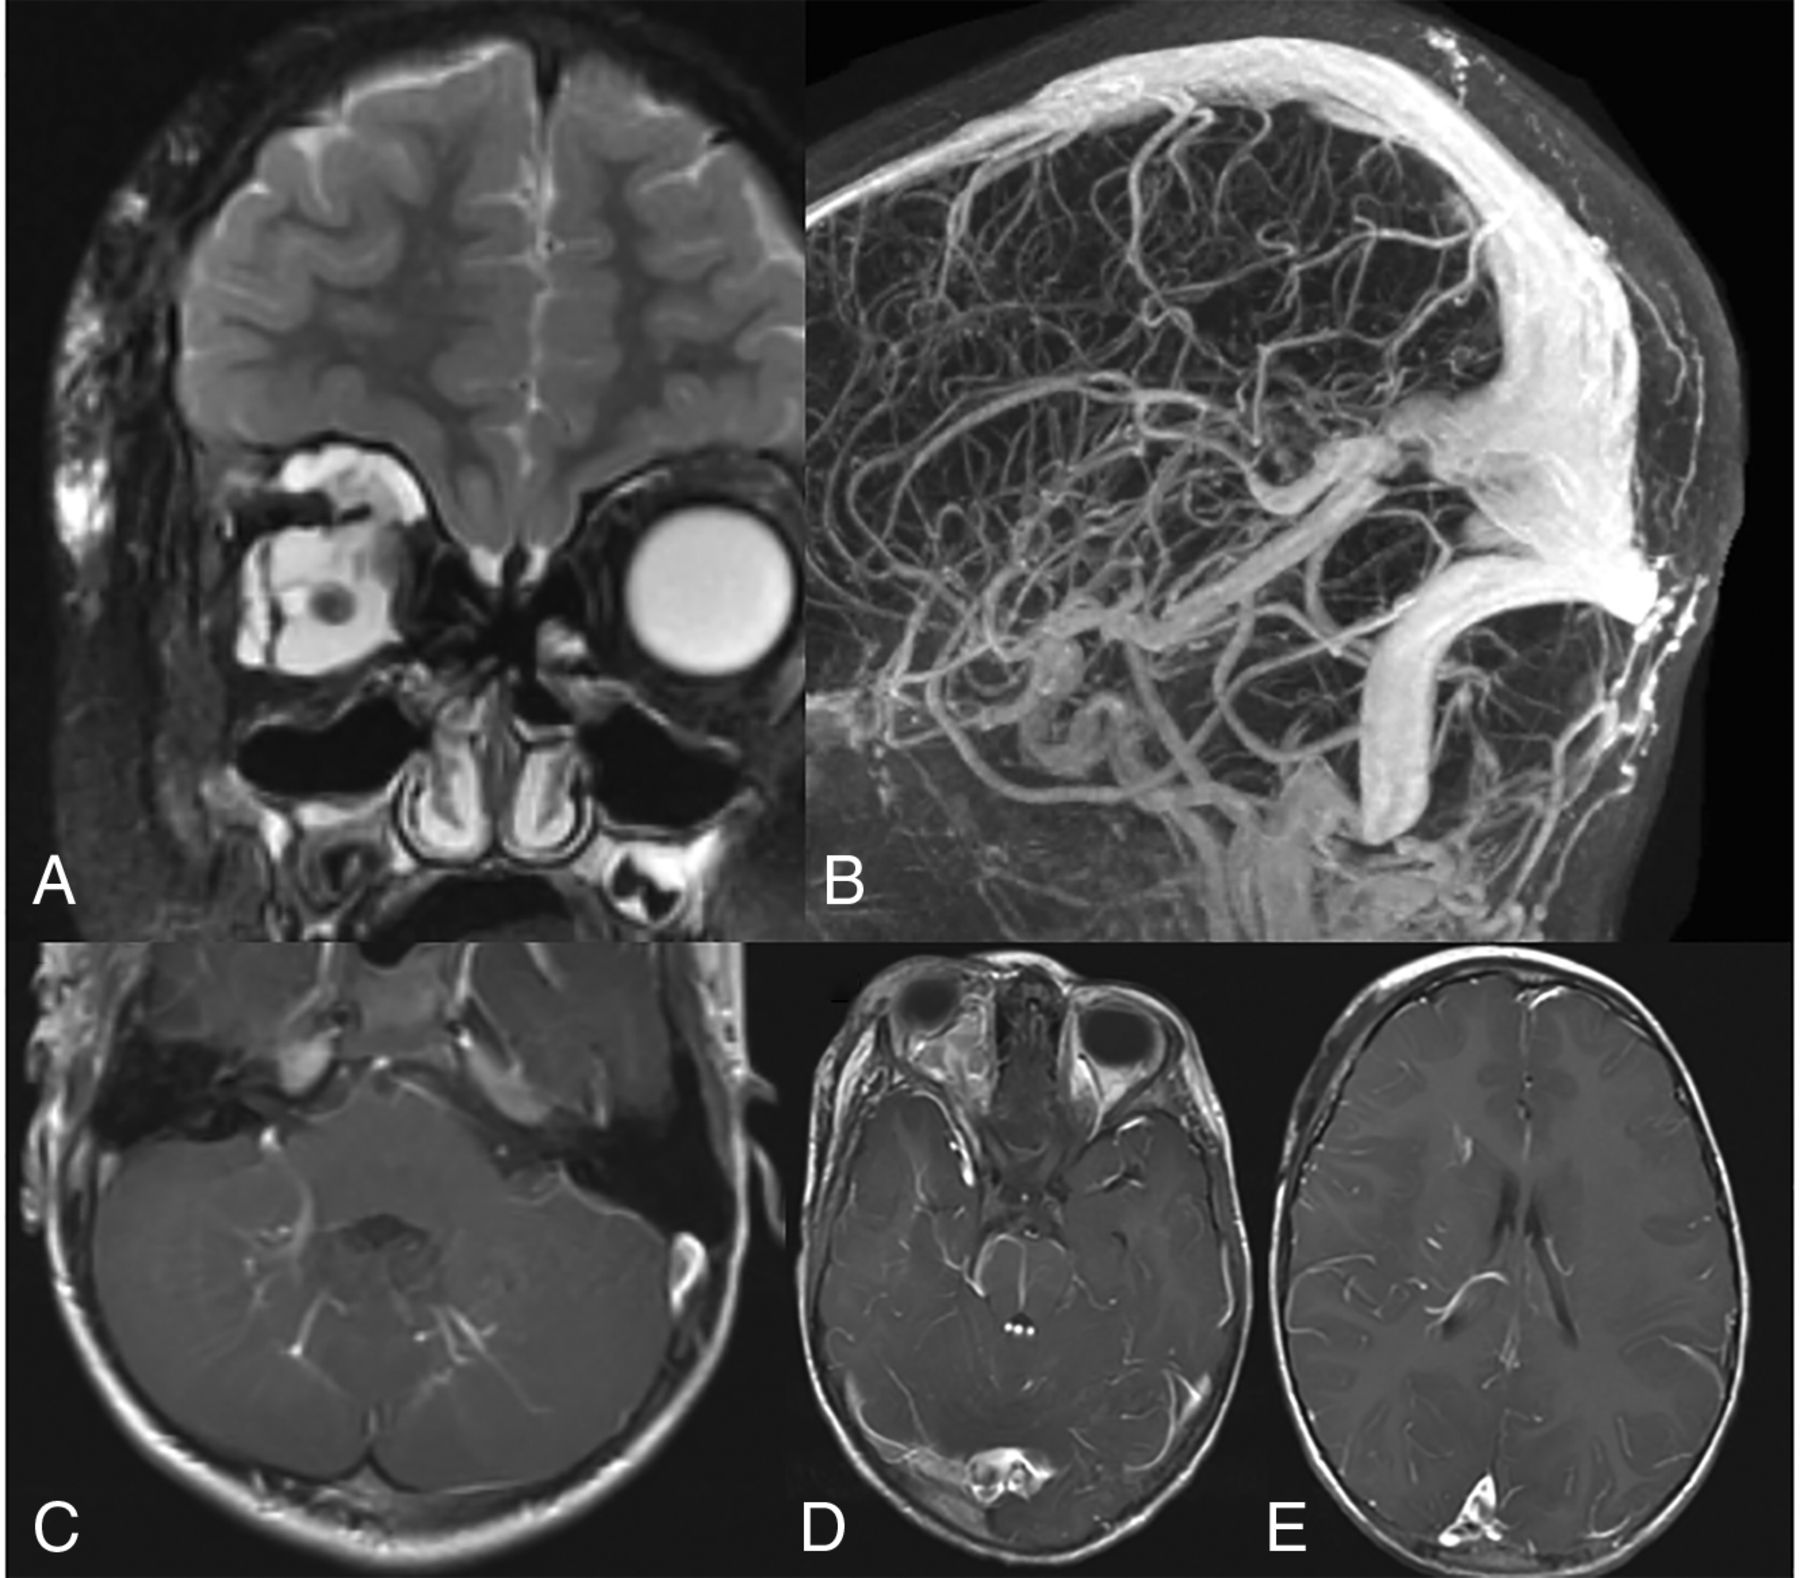

A 5-year-old child with history of right orbital venous malformation. A, T2 with fat saturation MR imaging shows a large venous malformation involving the right orbit and face. B, MRV shows a markedly ectatic torcula, which includes the entirety of the straight sinus. C–E, T1 postcontrast MRIs show multiple developmental venous anomalies, including the bilateral cerebellar hemispheres, brain stem, right temporal lobe, and right frontal lobe.